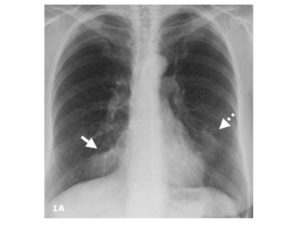

Учитывая, что признаки плеврита могут длительное время носить неспецифический характер, для подтверждения диагноза сбора анамнеза недостаточно. Обязательно проводится пальпация, перкуссия и аускультация для выявления шумов.

К инструментальным методам диагностики относят: — рентген, рентгенограмма, КТ, КТ с контрастированием, УЗИ, ЭКГ, тораскопия.